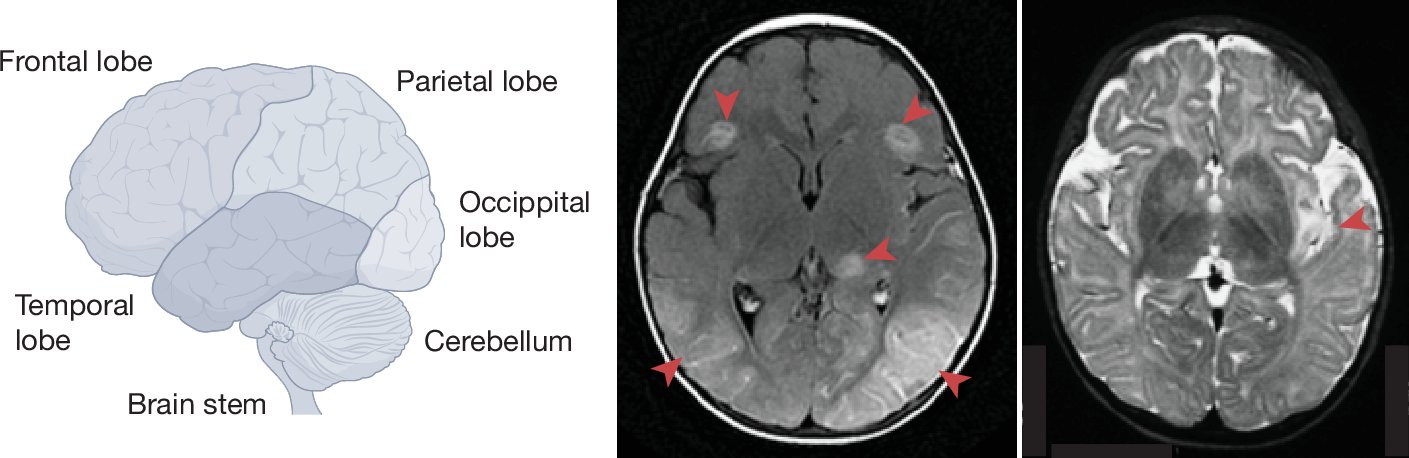

1/ Excited to share our study @SciImmunology introducing that autosomal recessive RIPK3 deficiency impairs #CellDeath -dependent control of #herpesvirus HSV-1 in cortical neurons, underlying herpes simplex #encephalitis (HSE) #RareDiseases

1/ We are happy to share our report of inherited RIPK3 deficiency in a child with HSV-1 encephalitis (HSE) in @SciImmunology (doi.org/10.1126/sciimm…­­­­­). HUGE thanks to all collaborators (list below)!

1) Delighted to share our review on Genetic Defects of Brain Immunity in Childhood Herpes Simplex Encephalitis (HSE), just out @Nature. Our expedition began in 2003, searching for monogenic defects underlying HSE. nature.com/articles/s4158…

1) Just out @Nature today! We show that human TMEFF1 is a restriction factor for #Herpes simplex virus 1(HSV1) in the brain, by limiting NECTIN1—HSV1-gD mediated HSV1 entry into cortical neurons. TMEFF1 defect can underlie HSV1 #encephalitis. nature.com/articles/s4158…

A novel disease-causing gene of herpes simplex encephalitis ( #HSE ): #TMEFF1, which inhibits the neurological entry of HSV-1 via interacting NECTIN-1 (a key HSV-1 receptor). Thrilled to have contributed to this amazing work!